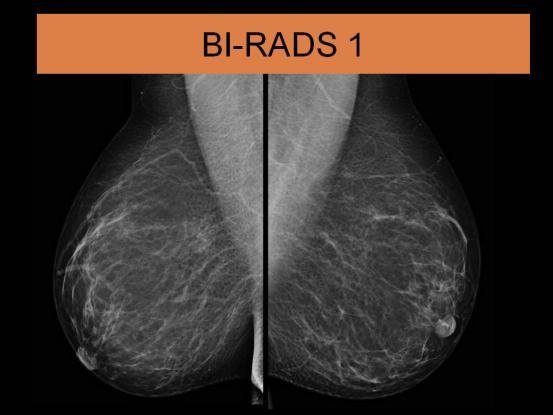

BI-RADS 1级 表现为双乳对称,无肿物,无结构扭曲,无可疑钙化,这一级的恶性可能性为0%;常规体检查看即可;

BI-RADS 1级